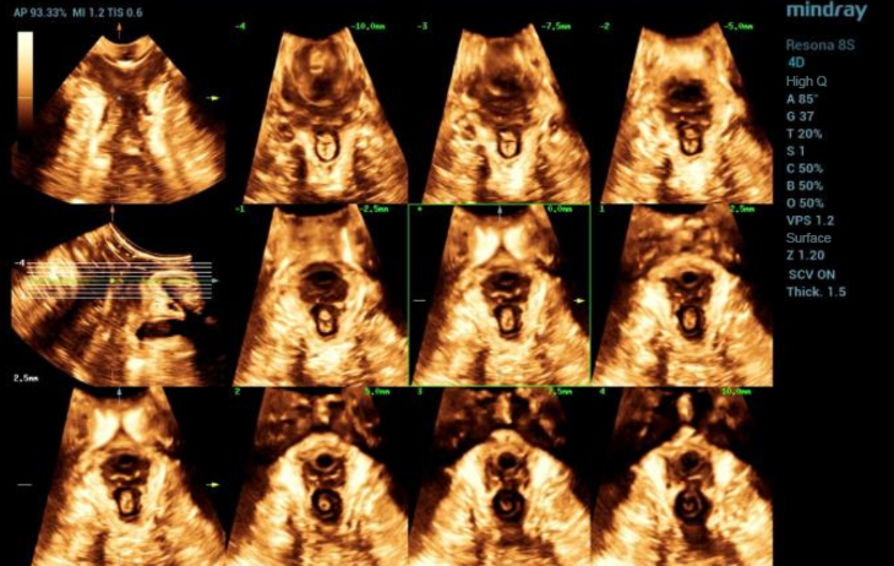

Mindray commenced its first #Nuewa Club Meeting in Bucharest, Romania!

Bajo el tema ŌĆ£inspirando el cuidado de la salud de la mujerŌĆØ, se llev├│ a cabo en la Ciudad de Panam├Ī la primera conferencia de Nuewa Club en Latino America.?